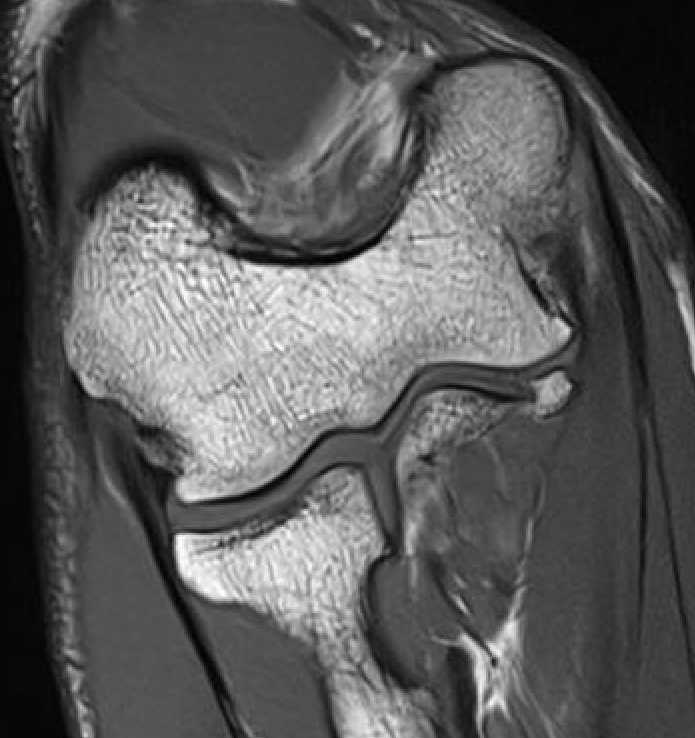

High grade partial distal UCL tear

PRLIPRLI